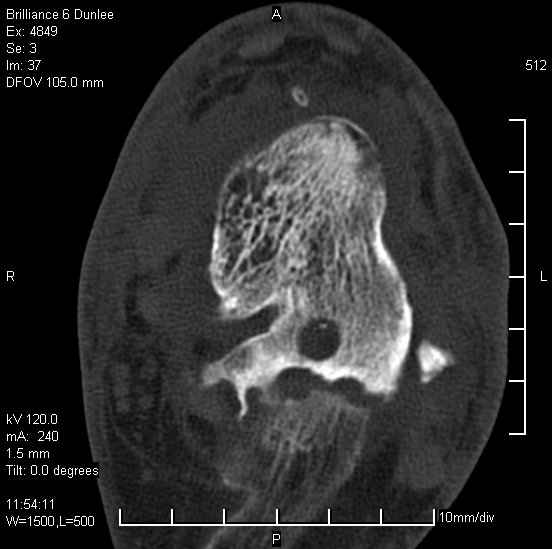

Асептический некроз таранной кости.

На лечении находится пациент 35 лет. Травма в сентябре 2008 г.- открытый вывих таранной кости

В день травмы ПХО, вправление вывиха, трансартикулярная фиксация. Рана зажила первично. С января нагрузка на конечность. С конца апреля- болевой синдром. На рентгенограммах и КТ признаки ас. некроза таранной кости, артроз подтаранного и голеностопного суставов.

У больного тотальный ас. некрох блока таранной кости, заинтересованы голеностопный и подтараный суставы. Эндопротезирование маловероятно на некротизированную кость. Изолированный подтаранный артродез таран не спасет.При артродезе всю некротизированную кость придется убрать.А далее замещение либо за счет большеберцовой кости, или удлинение на регенерате.